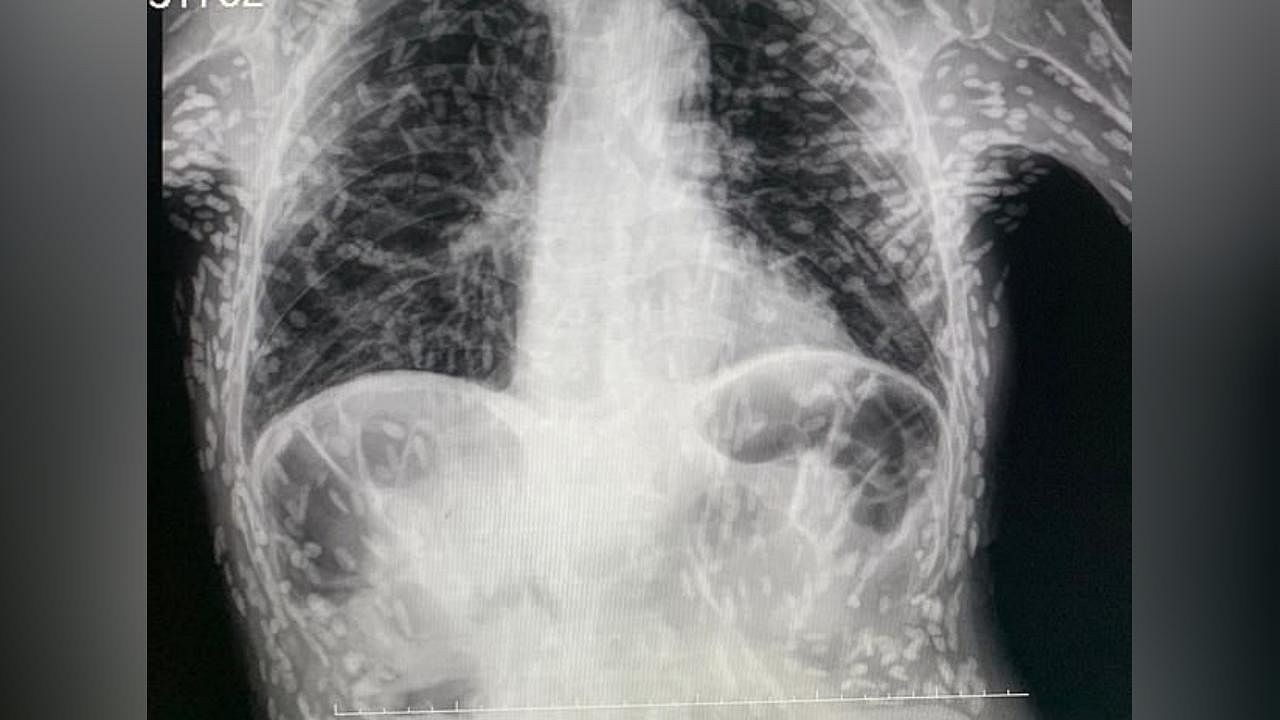

Hastanın röntgeninde yüzlerce beyaz nokta tespit edildi. Bu beyaz noktaların parazitlerin kireçlenmiş kalıntıları olduğu ortaya çıktı.